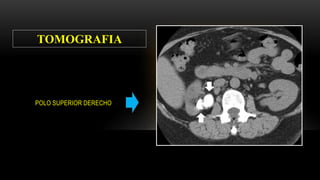

Se solicita el día 15/04/2015………TEM ABDOMINAL CON CONTRASTE

 RIÑON DERECHO: disminuido de tamaño, mide 7 cm, muestra parénquima adelgazado( laminar)

y con calcificaciones, tenue captación de contraste, no lesiones solidas ni quísticas, no litiasis

cálcica, los sistemas colectores dilatados, no hay excreción de sustancia de contraste

 RIÑON IZQUIERDO: localización y tamaño normal, con dilatación de grupos caliciales, se observa

menor captación de contraste, disminución de la diferenciación corticomedular, retardo en la

excreción dela sustancia de contraste, uréter izquierdo visualizado no dilatado, no litiasis.

 VEJIGA: pequeña, no litiasis, engrosamiento irregular de la mucosa.

 No adenopatías retroperitoneales

SE CONCLUYE:

 SIGNOS TOMOGRAFICOS QUE ESTAN EN RELACION CON PIELONEFRITIS CRONICA

IZQUIERDA. CONSIDERAR ORIGEN BACTERIANO, TBC entre otras

 EXCLUSION RENAL DERECHA.

 SIGNOS PATOLOGIA INFLAMATORIA VESICAL

POLO SUPERIOR DERECHO

TOMOGRAFIA

CALICES DILATADOS

CORTEZA ADELGAZADA